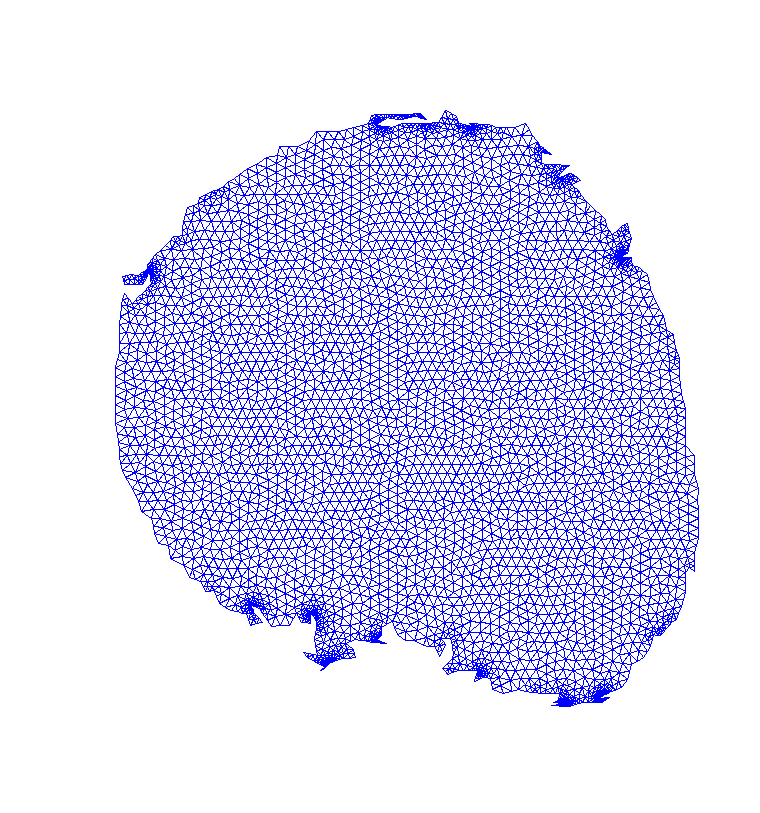

To reduce computational cost and get even more accurate results, we may create a Finite Element (FE) grid on the area of interest rather than on the image boundaries. For illustration, we consider the MR-images and shown on the top/left and bottom/left of Fig. 4, respectively. We automatically produce a mesh on the breast boundaries (see on the left of Fig. 5). The segmentation for and for is shown on the center and right of Fig. 5, respectively.

This FE approach can be easily adapted to other images, for example in Fig. 6 left, we apply this approach for segmenting a ventricle MRI heart image, taken from Angenent2006 with permission from1. In the center of Fig. 6, the FE mesh is shown and on the right of the figure, we see the segmentation of the adaptive eigenspace using FE. As discussed in Rem. 1, we do not always get a binary segmentation, but this is easy to get using a standard threshold.